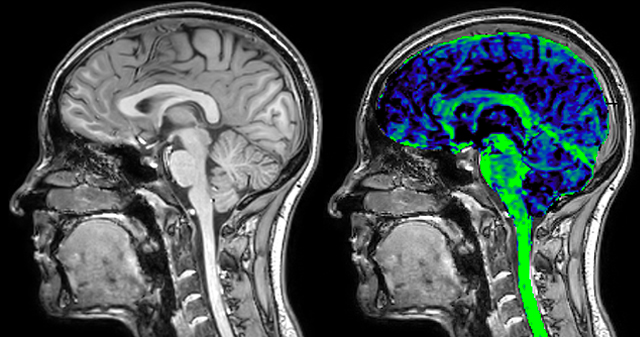

of limiting MWI to the brain, even without the cerebellum, we can now spend about the same amount of time and scan the whole brain and the cervical spinal cord, which is a huge boost for us.” Dr. Rauscher says, “For MWI we perform 3D T2 with 32 or more echoes. This used to take a long time, but with Compressed SENSE we can decrease this to ten minutes for the whole head. Because of the large field of view (FOV) on the readout direction, we even get information from the brainstem, which we previously missed when we were using the GRASE approach. Having the whole head scan is nice because it has spatial resolution, orientation and FOV that are comparable to the standard 3D clinical MS scans, including the FLAIR and 3D T2, and a 3D T1 for brain volume.”

T1 - Weighted, Myelin Water Fraction Superimposed

Spinal cord coverage

Smaller, more isotropic voxels

Excellent detail in quantitative maps

Images courtesy of Adam Dvorak, Department of Physics and Astronomy, University of British Columbia

The techniques for measuring myelin have changed a lot over the years. “Since we are using the Elition, our myelin water images are much better. We're now acquiring 1 x 2 x 5 mm voxels and displaying at 1 x 1 x 2.5 mm. For a whole brain we can now measure the fraction of water in the myelin component in only about five or six minutes,” Dr. MacKay says.